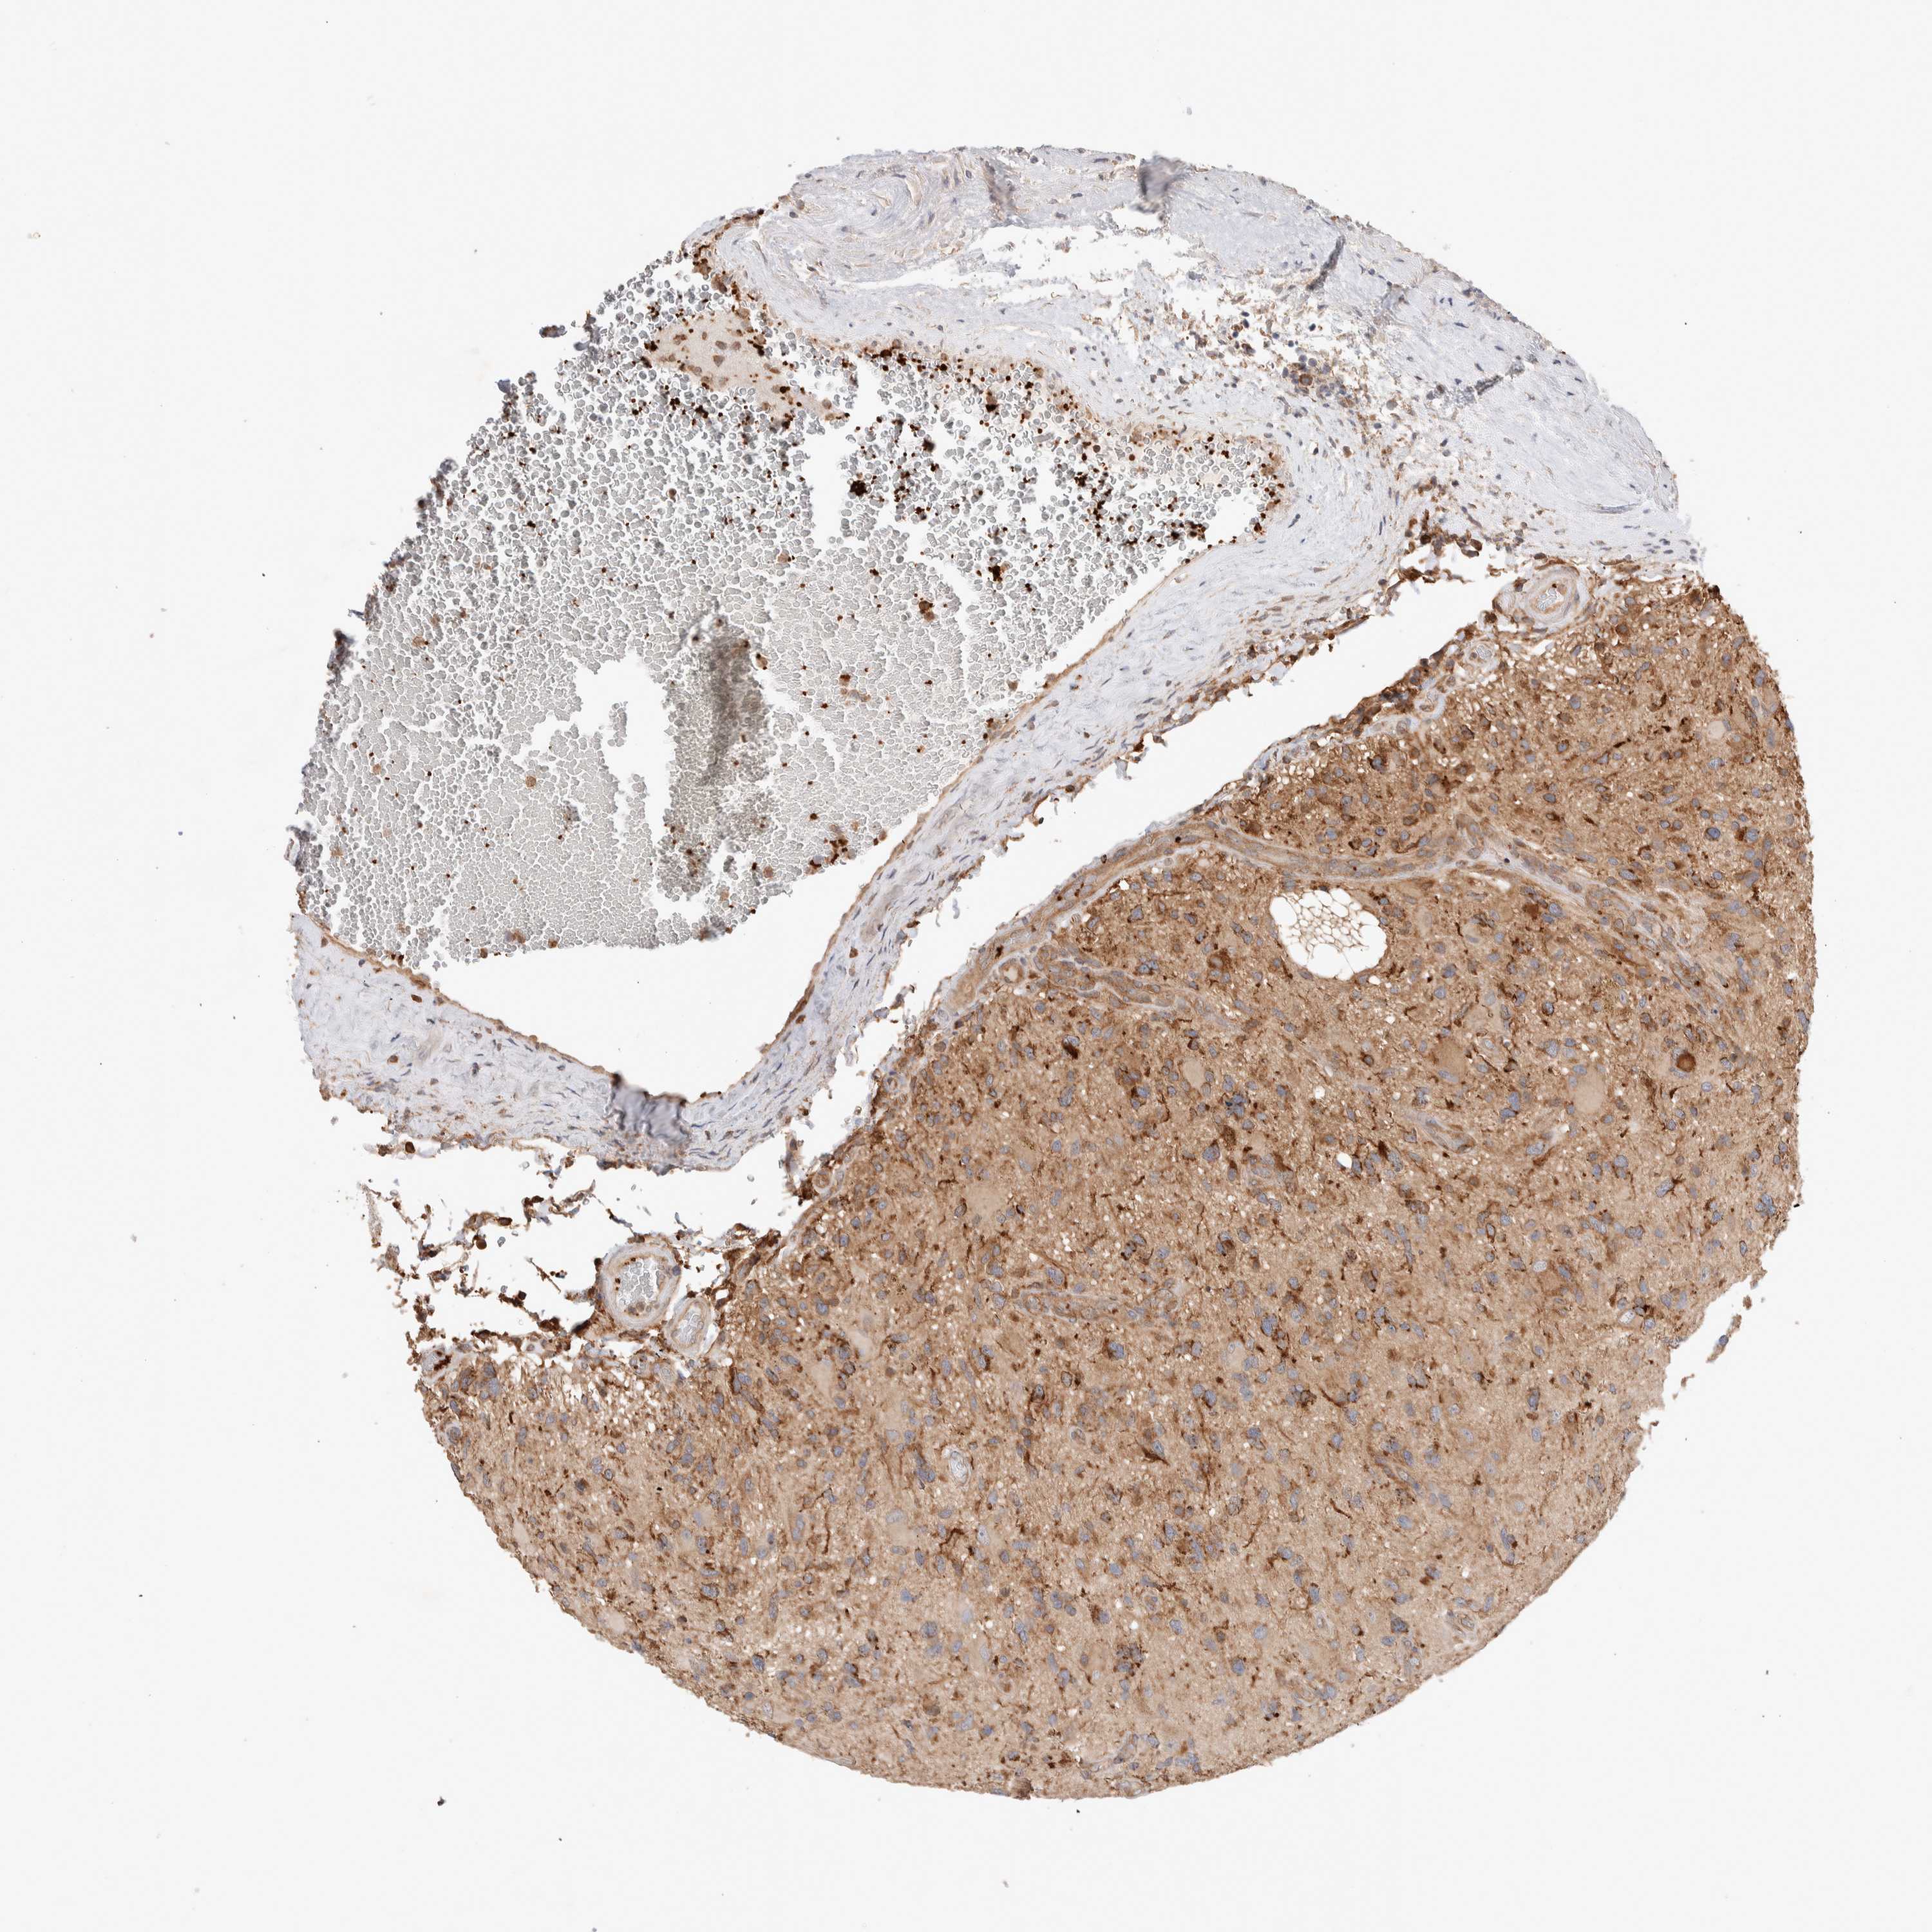

GLIOMA - Protein expressioni

A mouse-over function shows sample information and annotation data. Click on an image to view it in a full screen mode. Samples can be filtered based on level of antibody staining by selecting one or several of the following categories: high, medium, low and not detected. The assay and annotation is described here.

Note that samples used for immunohistochemistry by the Human Protein Atlas do not correspond to samples in the TCGA dataset.

Antibody stainingi

Antibody staining in the annotated cell types in the current human tissue is reported as not detected, low, medium, or high, based on conventional immunohistochemistry profiling in selected tissues. This score is based on the combination of the staining intensity and fraction of stained cells.

Each image is clickable and will lead to virtual microscopy that enables deeper exploration of all samples and also displays staining intensity scores, fraction scores and subcellular localization as well as patient and tissue information for each sample.

Antibody HPA023938

Antibody HPA023945

Antibody HPA024011

Antibody CAB020841

Staining

High

Medium

Low

Not detected

Intensity

Strong

Moderate

Weak

Negative

Quantity

>75%

75%-25%

<25%

None

Location

Nuclear

Cytoplasmic/membranous

Cytoplasmic/membranous,nuclear

Glioma, malignant, High grade

Glioma, malignant, Low grade